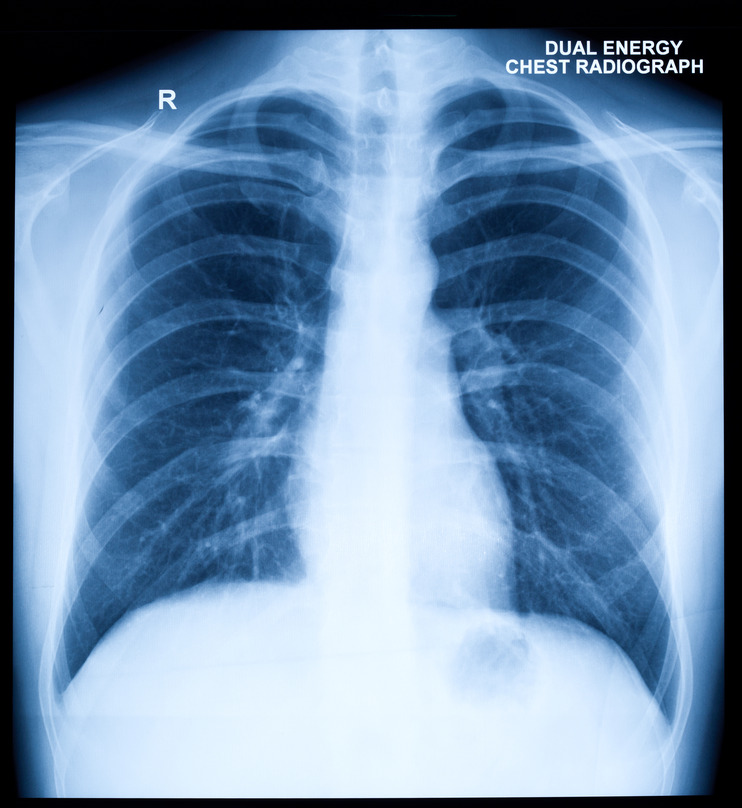

X Ray Kub Stock Photos, Pictures & Royalty-Free Images – iStock

Chest X-Ray | Cardiovascular Medical Group of Southern California